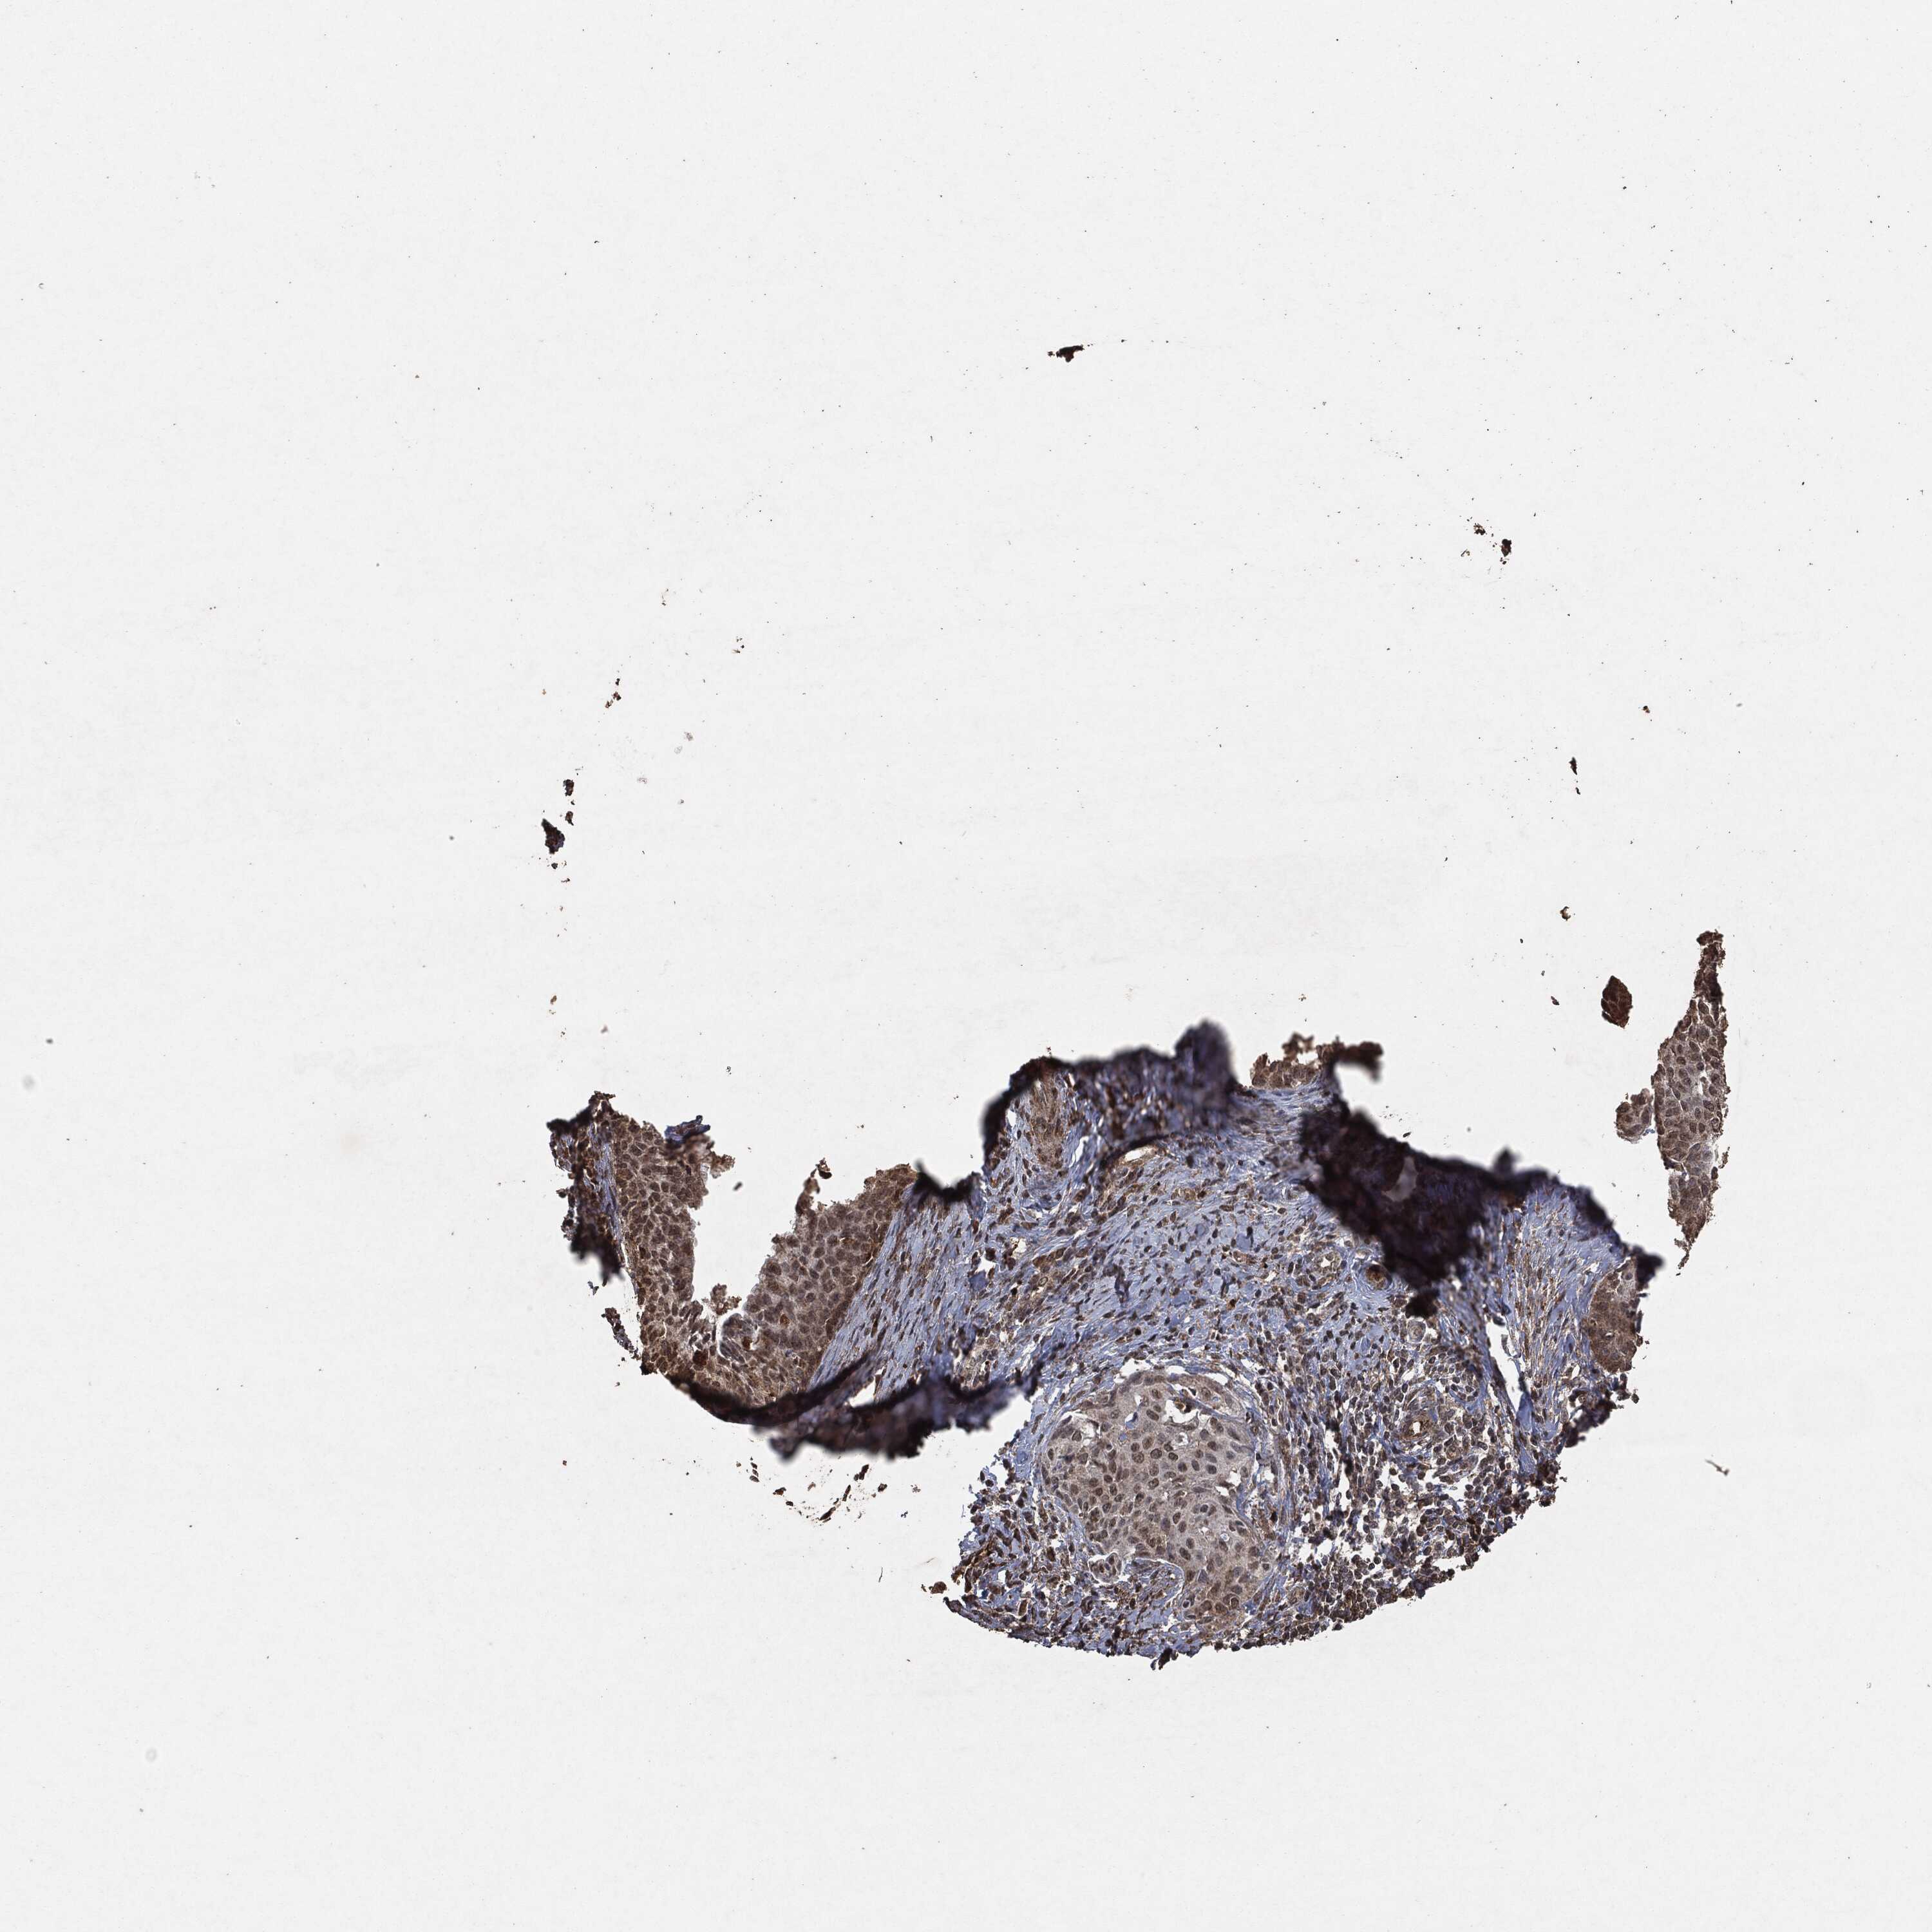

CERVICAL CANCER - Protein expressioni

A mouse-over function shows sample information and annotation data. Click on an image to view it in a full screen mode. Samples can be filtered based on level of antibody staining by selecting one or several of the following categories: high, medium, low and not detected. The assay and annotation is described here.

Note that samples used for immunohistochemistry by the Human Protein Atlas do not correspond to samples in the TCGA dataset.

Antibody stainingi

Antibody staining in the annotated cell types in the current human tissue is reported as not detected, low, medium, or high, based on conventional immunohistochemistry profiling in selected tissues. This score is based on the combination of the staining intensity and fraction of stained cells.

Each image is clickable and will lead to virtual microscopy that enables deeper exploration of all samples and also displays staining intensity scores, fraction scores and subcellular localization as well as patient and tissue information for each sample.

Adenocarcinoma, NOS

Squamous cell carcinoma, NOS